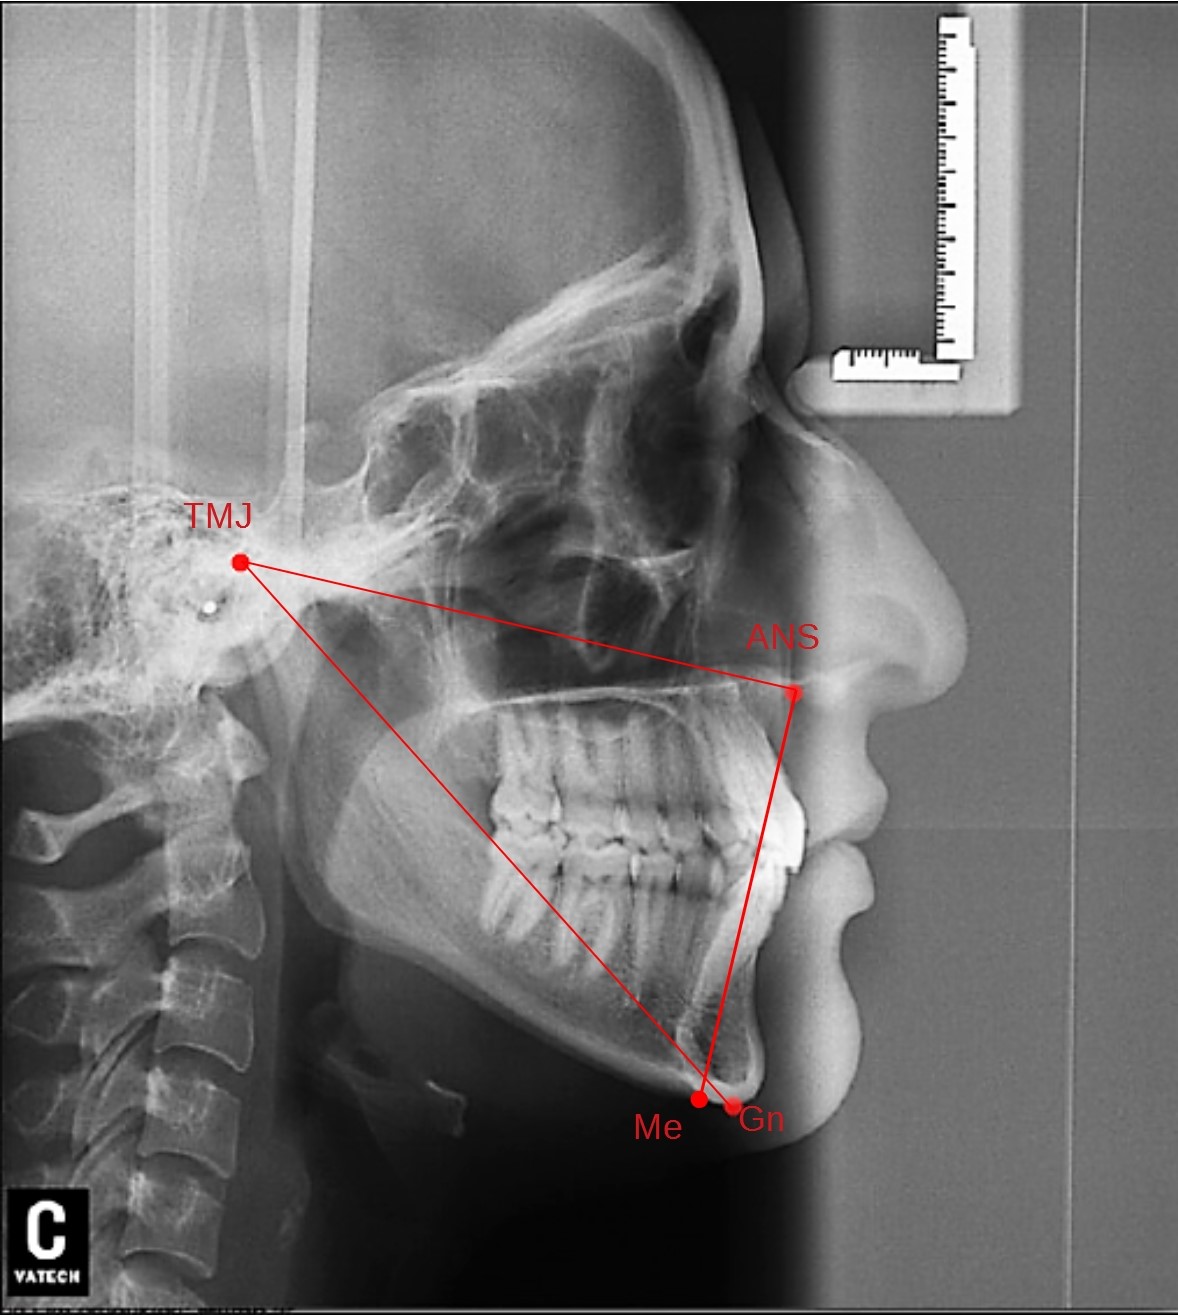

Introductionː Lateral cephalometry is commonly used to analyse craniofacial morphology, soft tissue profile and the direction of facial growth in an attempt to predict the possibilities and limits of orthodontic therapy.

The aim of the study was to present the most frequently used cephalometric measurements to assess the skeletal class on a lateral cephalometric headfilm.

Conclusionsː 1. ANB angle cannot be used as the only indicator of sagittal skeletal discrepancy. 2. WITS appraisal is independent of the variability of cranial base structures, thus may be an important supplement to the diagnosis, although it depends on the variability of the occlusal plane. 3. APDI can reliably distinguish between class I, II and III malocclusions.